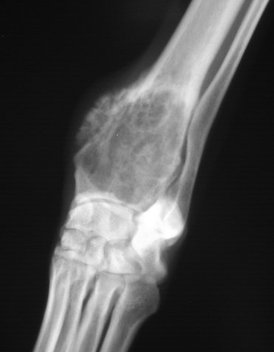

A bone cancer known as osteosarcoma is genetically similar in dogs and human children, according to the results of a study published today by Tufts University and the Translational Genomics Research Institute (TGen), an affiliate of City of Hope. The findings could help break the logjam in the treatment of this deadly disease, which hasn’t seen a significant medical breakthrough in nearly three decades.

OS is an aggressive disease and the most commonly-diagnosed primary bone tumor in dogs and children. Though a relatively rare cancer in humans — with fewer than 1,000 cases each year — OS strikes more than 25,000 dogs annually.